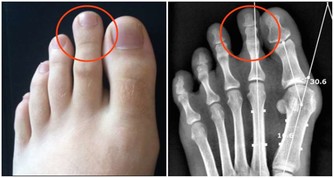

七、在抬腳時,脊椎保持水準,全身肌肉富有彈性,氣血順暢,各關節自會增生骨髓,脊椎兩旁神經恢復平常傳導作用,何來關節退化,或長骨刺?及壓迫神經的病痛呢?